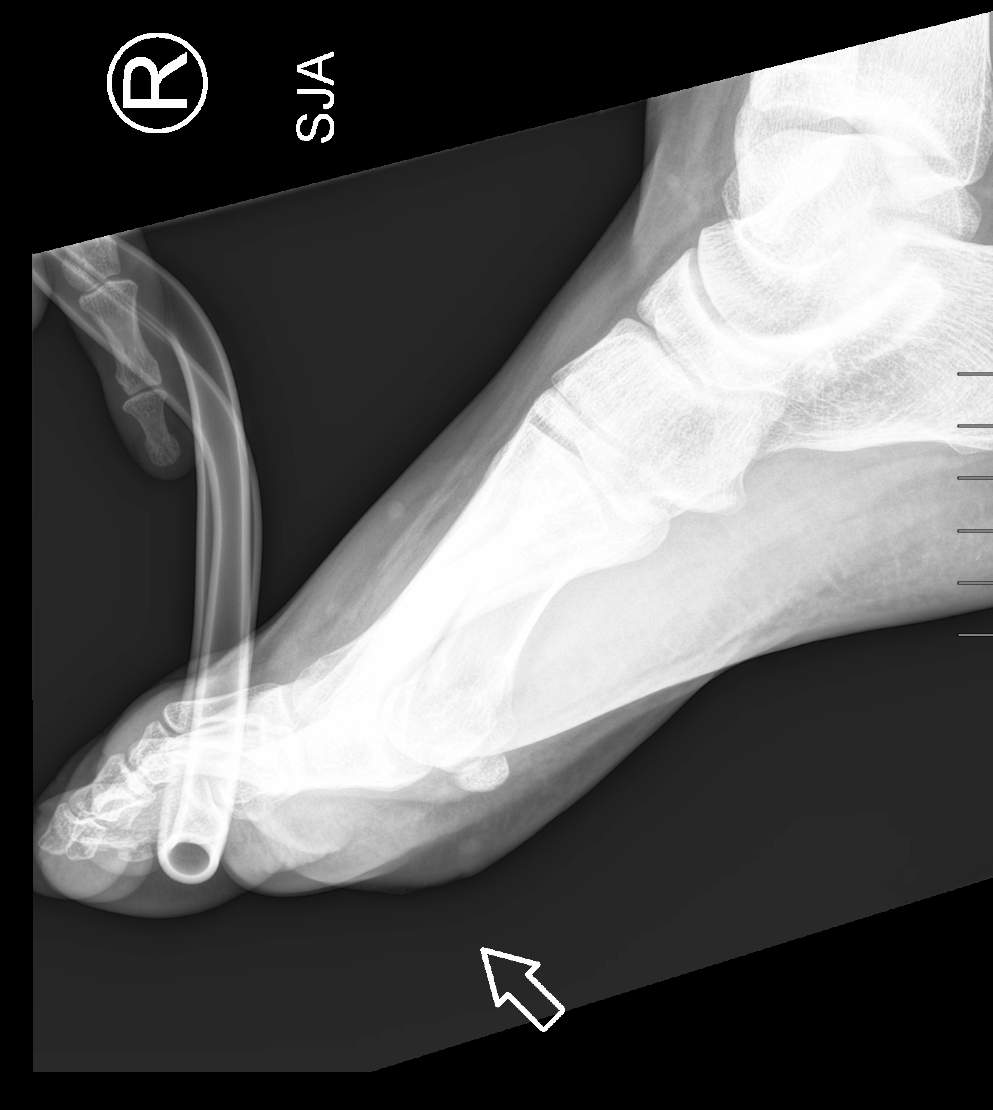

Info Images Findings Impression Reco/Acuity Case Images View Images / Launch Visage Case Notes History 2-month-old presents with decreased right arm movement, increased fussiness, and increased sleepiness for 2 days. Suspected non-accidental trauma. Exam Skeletal survey Prior Study none Dicom View Reference Material

Section 1 Submit Findings CB1550 Findings Skeletal Survey - Technique Check Skull AP/Lat Yes No Cervical and Thoracolumbar spine Yes No Chest X-Ray Yes No Ribs – Left/Right Oblique Yes No Abdominal X-Ray Yes No Pelvis with both hips Yes No Bilateral Humerus, Forearm, Hand Yes No Bilateral Femur, Tibia/fibula, feet Yes No Any additional lateral views of the extremities Yes No The exam is over or under penetrated. Yes No The exam may or may not be limited by overlying structures or soft tissues, body habitus, patient positioning, support devices, or motion. Yes No The area of concern is indicated by the patient, technologist, or care provider. Yes No The area of concern is included on the exam. Yes No Soft Tissues There is soft tissue swelling, indistinctness of fat/muscle planes, gas, or laceration in the area of clinical concern. Yes No There is an effusion, fat pad displacement, or fat fluid level. Yes No There is a radiodense or lucent foreign body. Yes No There are other densities, calcifications, post-surgical changes, or support devices in the soft tissues. Yes No Any support lines/tubes. Yes No Bone There is a break or interruption of the continuity of the cortical or cancellous bone. Yes No There is overriding of the trabeculae with apparent sclerosis. Yes No There is displacement of a fracture fragment. Yes No There is bowing of the bone in addition to the fracture at the apex of the bowed bone concerning for the greenstick. Yes No There is a spiral fracture of the leg concerning for toddler’s fracture. Yes No There is abnormal angulation or bulging of the cortical surface relative to the normal cortex which could be from a buckle or torus fracture. Yes No There is a displaced fragment which may be from avulsion by a tendon, ligament, or joint capsule or from a comminuted or other fracture. Yes No The stress trabeculae or other trabeculae of the cancellous bone are interrupted or otherwise abnormal. Yes No There is subperiosteal or endosteal reaction which could indicate a healing or subacute fracture or other abnormality. Yes No There is hard/soft callus formation. Yes No There is remodeling of the bone. Yes No There is a corner fracture or metaphyseal lesion that could be from nonaccidental trauma. Yes No There are multiple fractures of different ages. Yes No There are vertebral body/spinous process fractures. Yes No There are rib fractures. Location - posterior or lateral. Yes No There is scapular/sternal fracture. Yes No There are fractures of the digits. Yes No There are wormian bones. Yes No There are intrasutural bones. Yes No There is metaphyseal abnormality (lucencies, increased density, erosion) which may be from something other than injury such as stress, metabolic disease (e.g. rickets with loss or distortion of the zone of the provisional calcification), neoplasm (e.g. leukemia), heavy metals, inflammation, or infection. Yes No There are metaphyseal spurs. Yes No There are bony deformities involving multiple bones. Yes No The bones are gracile. Yes No There are non-healing fractures. Yes No There is/are focal or multifocal lytic/lucent, blastic/sclerotic or mixed density lesion(s) or other abnormality. Yes No Overall bone density is increased or decreased with or without thinning or thickening of the cortical or cancellous bone. Yes No Growth plates, ossification centers, apophyses The growth plate(s) is/are abnormal. Yes No There is widening of the physis from a fracture with or without displacement of the epiphysis (Salter-Harris I). Yes No There is a fracture through the physis which then extends into the metaphysis with or without angulation or displacement (S-H II). Yes No There is a fracture through the physis which then extends into the epiphysis and is intra-articular, with or without angulation or displacement (S-H III). Yes No There is a fracture through the metaphysis, physis, and epiphysis which extends into the joint space with or without angulation or displacement (S-H IV). Yes No There is narrowing of the physis from a compression fracture (S-H V). Yes No The apophysis, epicondyle, secondary ossification center, or accessory ossicle is displaced or otherwise abnormal. Yes No The ossification centers are underdeveloped. Yes No Joints and alignment There is an effusion, fat pad displacement, or fat fluid level. Yes No The epiphysis or subchondral bone is fractured, interrupted, flattened, compressed, impacted, displaced, or otherwise abnormal. Yes No There is an intra-articular loose body or chondrocalcinosis. Yes No The joint is widened, narrowed, dislocated, malaligned, or incongruent. Yes No There is pseudoarthrosis. Yes No Other findings There are developmental changes or other anatomic variants or other existing conditions that may or may not be contributing to symptoms which can or should be further evaluated non-emergently or are otherwise incidental. Yes No The remainder of the exam is abnormal for age. Yes No The lungs show focal airspace opacity. Yes No There is pneumothorax. Yes No There is organomegaly. Yes No There is intra-abdominal calcification. Yes No There is displacement of the bowel loops. Yes No There is free intraperitoneal air. Yes No The bowel loops are dilated/obstructed. Yes No There is paraspinal soft tissue abnormality. Yes No